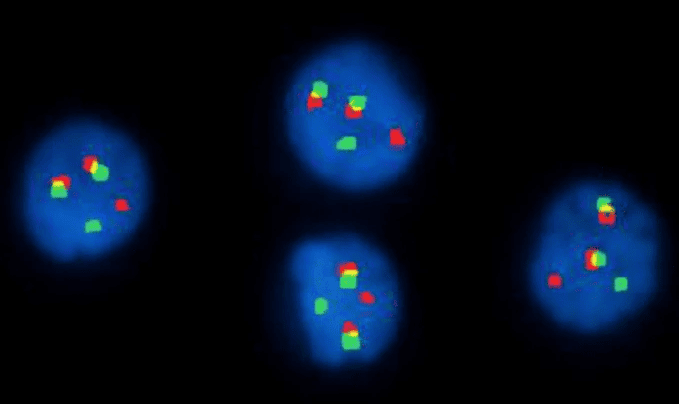

Fluorescence In Situ Hybridization (FISH)

This technique uses fluorescent probes that bind to specific DNA sequences on chromosomes. It’s particularly useful for identifying specific gene fusions, deletions, or translocations that may be too small to see with a standard karyotype, and can be used when cells don’t divide well enough for karyotyping, such as in multiple myeloma.

Interphase FISH with IGH/FGFR3 dual-fusion probes showing the t(4;14) translocation in multiple myeloma, a key finding in molecular and cytogenetic studies in hematology.